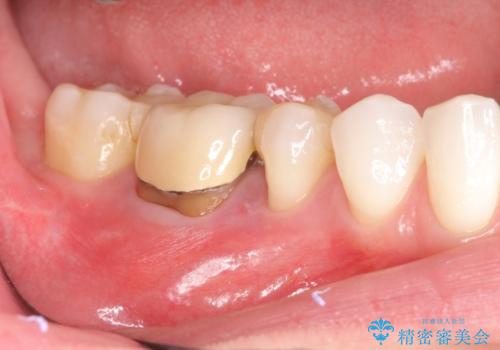

歯肉にできものがある、根管治療からセラミッククラウンまで

- 歯肉にできものがあるのを気にされて来院されました。

右下5,6間にフィステル(瘻孔)を認めました。デンタルより、右下5根尖に透過像を認め、フィステルに材料を入れてレントゲンにて確認したところ、右下5の根尖に到達しました。

右下5の神経は失活してしまっているため、根管治療の必要性を説明の上、根管治療をした後セラミッククラウンを入れていくこととなりました。